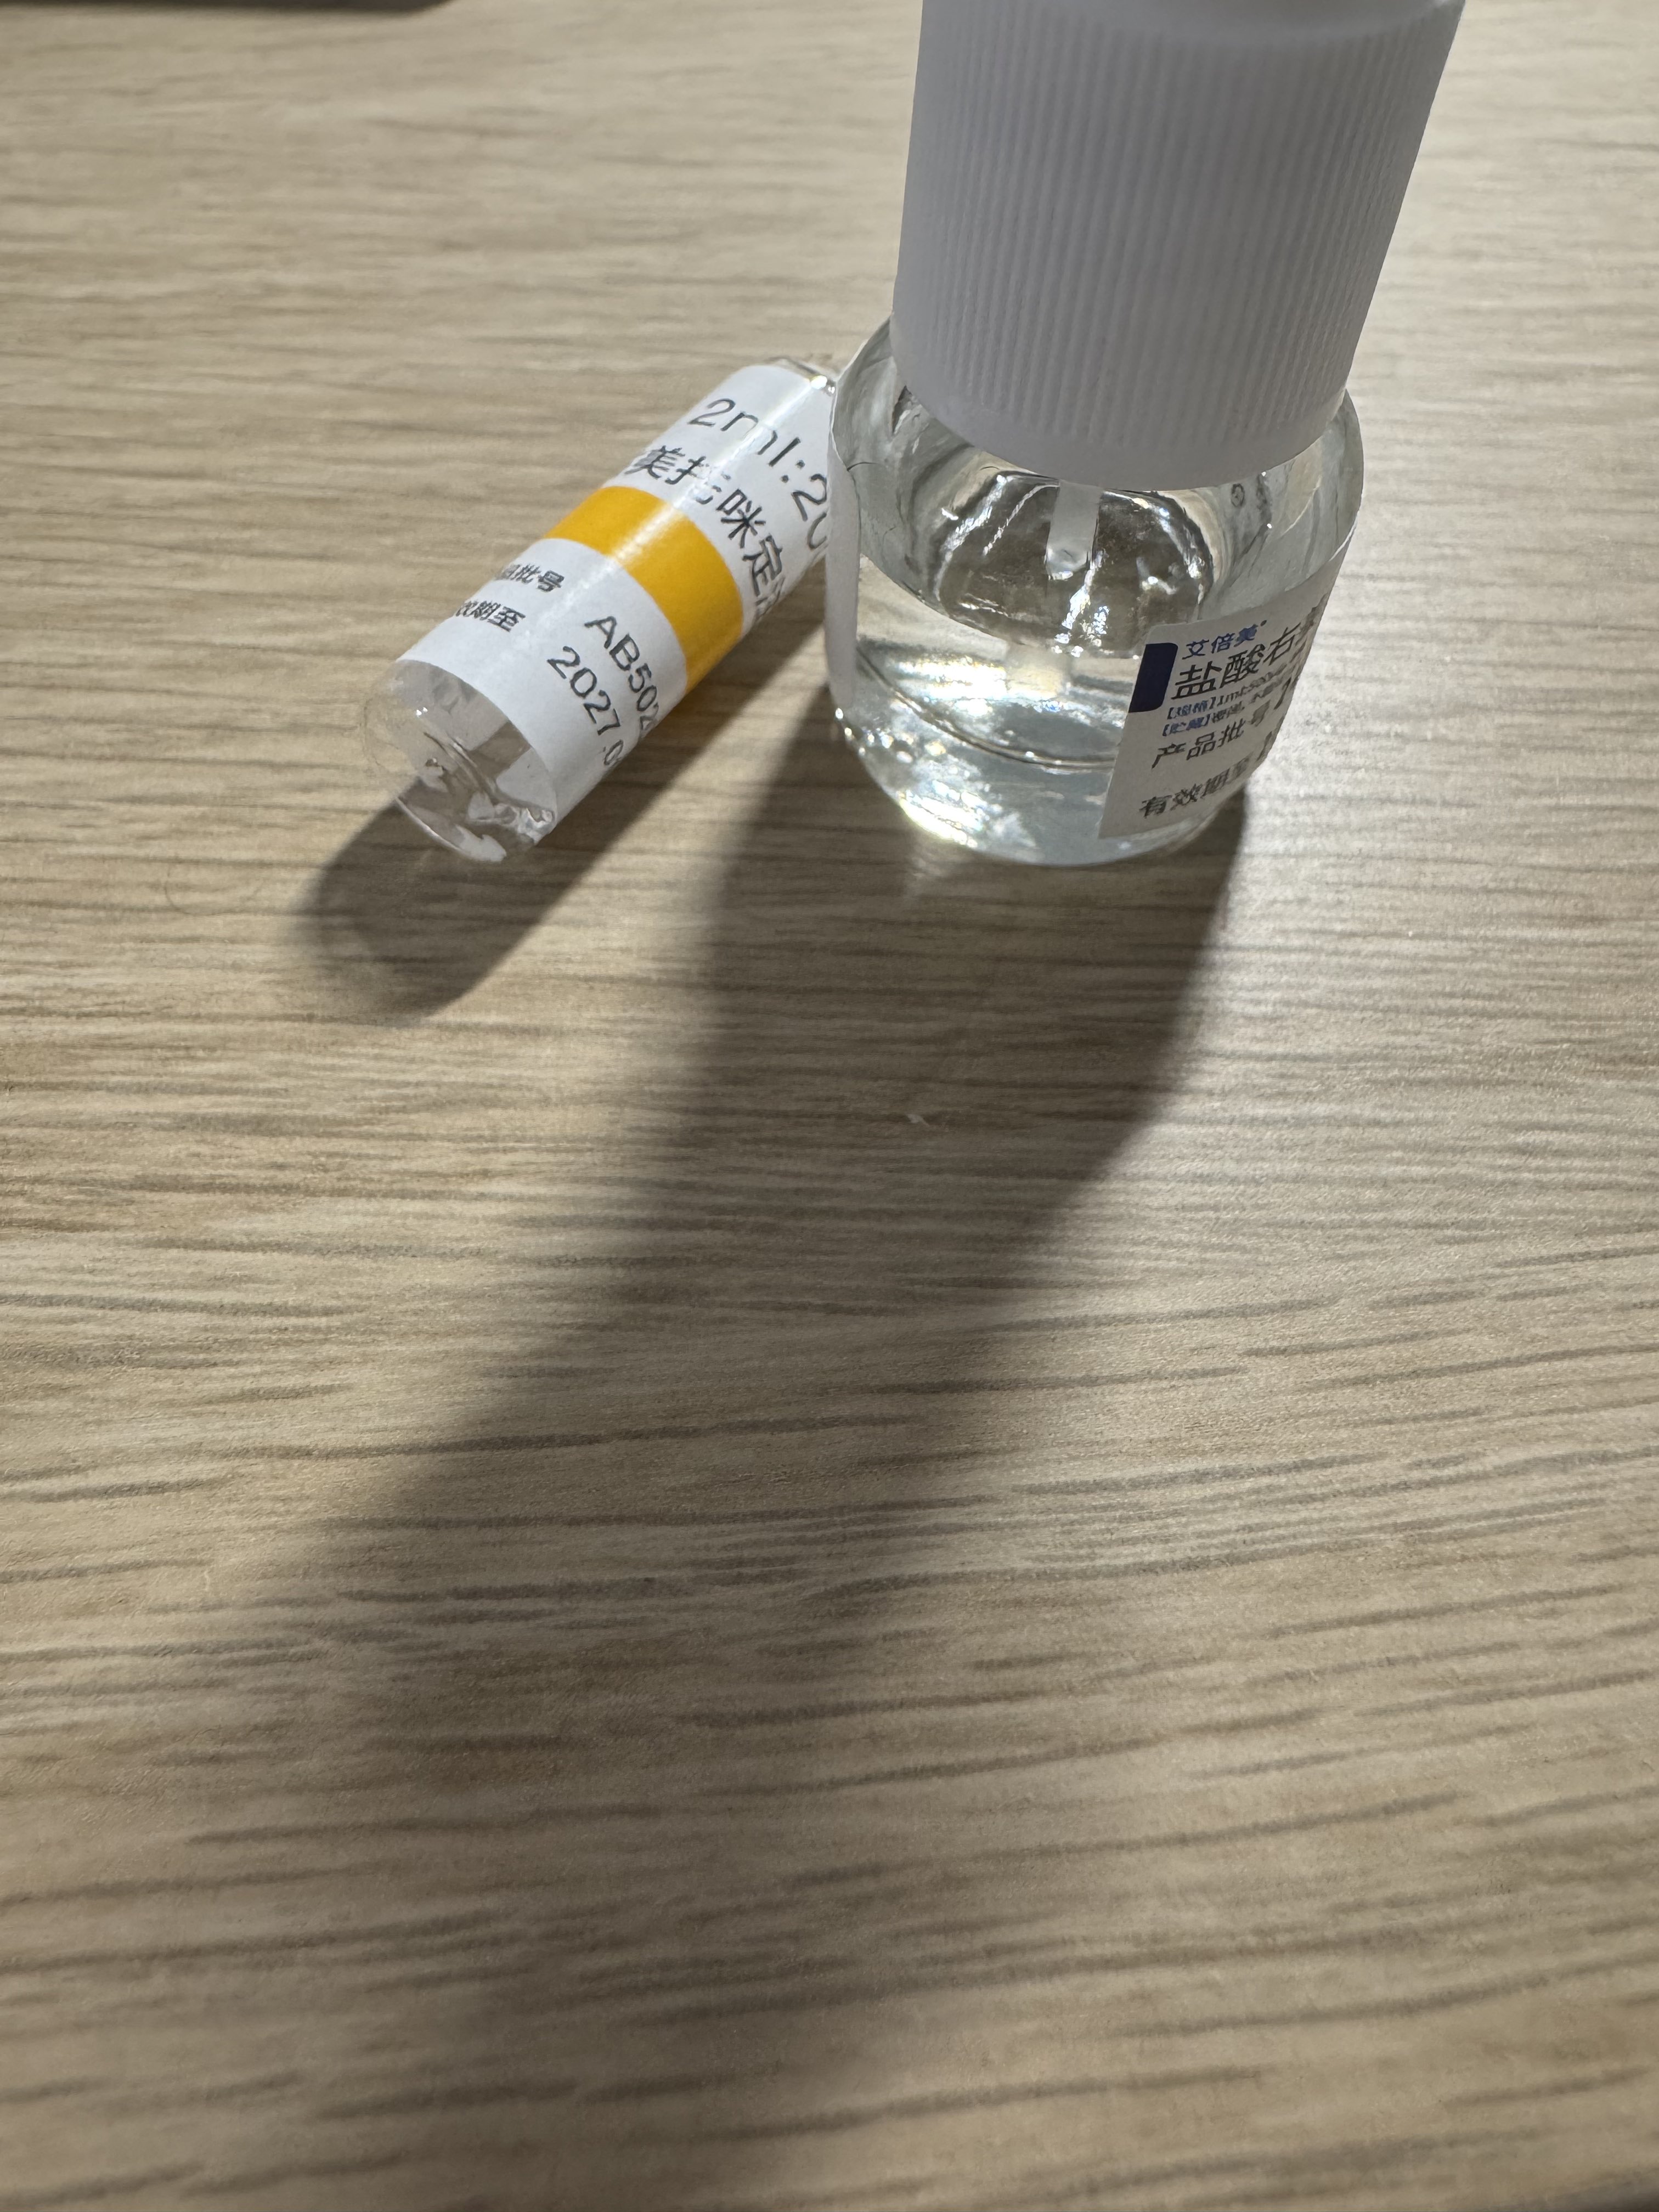

关于疤痕管理..?

因为皮肤比较容易过敏用不了疤痕贴这类的所以一般都用软膏或凝胶()

左边的只能用于已经愈合的创伤!右边的可以用于创面,还有人表皮因子生长凝胶或许也可以,都有不止祛疤的功能⬇️

曾经有一段时间一直在坚持用乳膏,在我这里的功能更像是一种仪式…有时候甚至可以对抗自伤冲动 https://t.co/PFB5AIisHE